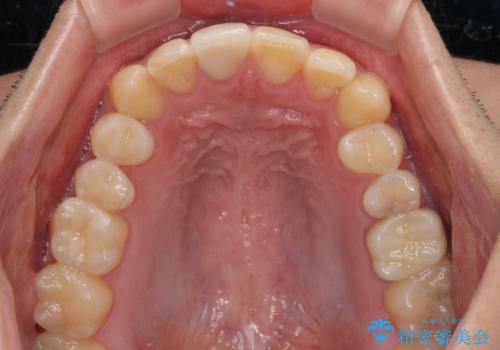

- 治療中の前歯と口腔内にある銀歯が気になるとのことで来院された患者様です。

土台に含まれている金属も含め、口腔内の金属は全て除去し、根管治療が必要な歯は根管治療を行い、オールセラミッククラウンやセラミックインレーにて治療することとしました。

途中来院されない時期があったため、初診から終了まで期間がかかりましたが、根管治療を行った歯の根尖病変はいずれも改善を確認することができました。

口腔内の金属が全てなくなり、患者様には大変満足していただきました。